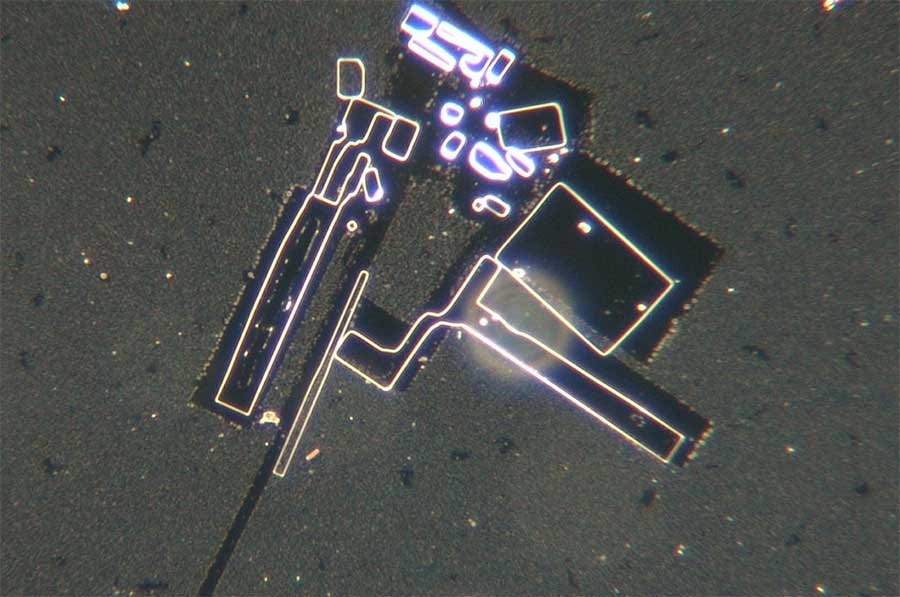

Generalmente solo después de la desecación de estas muestras o por calor pudieron observar algo verdaderamente terrorifico descrito como circuitería o algun tipo de bionanotecnología o nanotecnología que ensambla.

Ha pasado varios días identificando diferentes estructuras: desde filamentos que se forman a base de cristales de ADN , Morgellons , y extrañas formas de vida.

En un programa reciente, identificó algunas estructuras que parecen hojas largas y otras que son más vermiformes y aterradoras.

Este estudio recientemente publicado en Italia confirma una vez más las nanoestructuras de autoensamblaje en la sangre de personas inyectadas con C19. Los autores correlacionan los hallazgos de sangre con los síntomas del afectado. Por ejemplo, se discutió este caso:

Here are further self assembly nanostructures:

Estas 4 imágenes ilustran la variedad de fenómenos y objetos inusuales encontrados en la sangre de sujetos vacunados con Comirnaty BioNTech/Pfizer (Cortesía de Helen Krenn)MÁS

These substances, furthermore, “are visible under the dark-field microscope as distinctive and complex structures of different sizes, can only partially be explained as a result of crystallization or decomposition processes, [and] cannot be explained as contamination from the manufacturing process,” the researchers found.